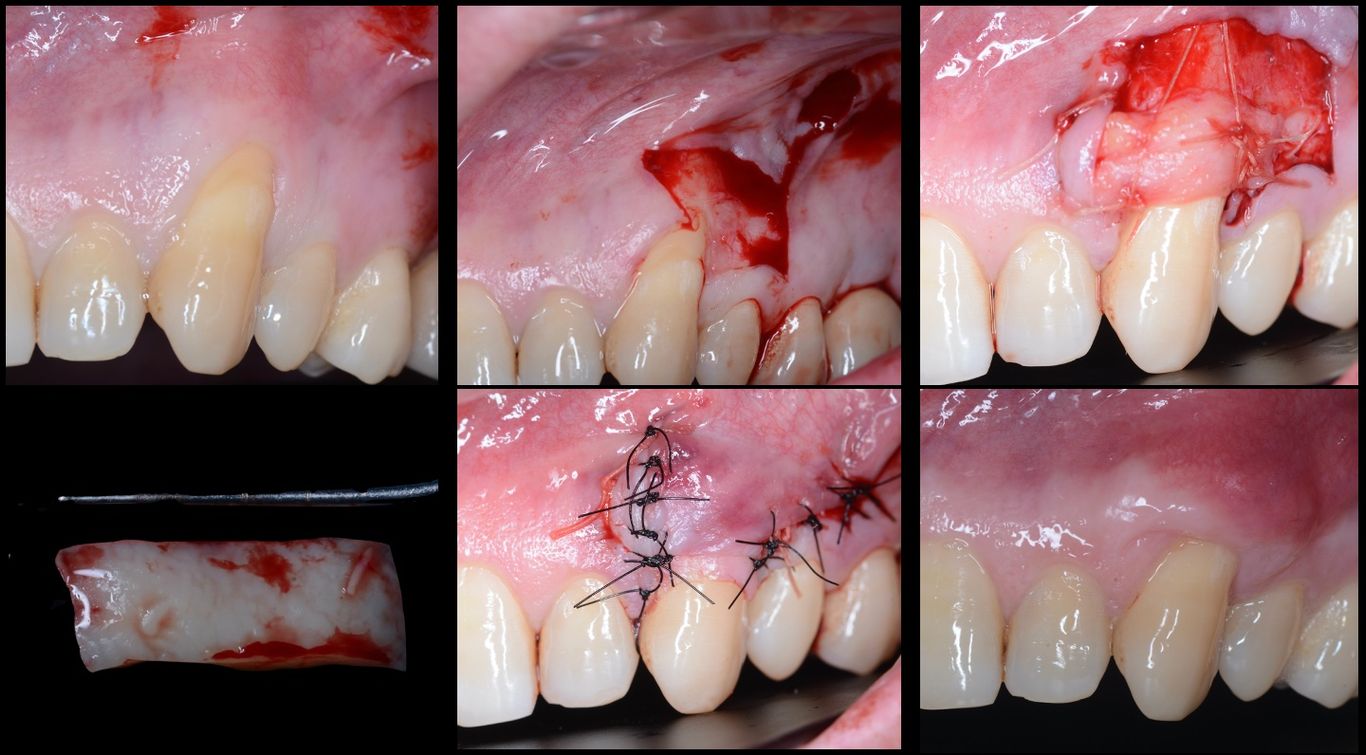

Cirugía Plástica sobre

dientes e implantes

Este curso eminentemente práctico te enseñará multitud de técnicas de Cirugía Mucogingival para que puedas garantizar el éxito en tus tratamientos y, además, que puedas ofrecer tratamiento a aquellos pacientes que terminen en tu consulta buscando una solución.